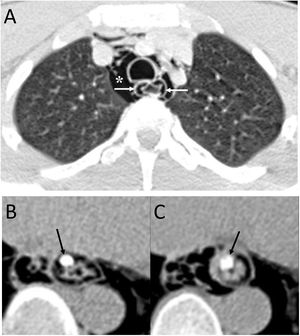

Bilateral spontaneous PTX, which represents 1.3% of spontaneous PTX, has also been described as a complication of a unilateral transthoracic puncture29 (Fig. 12).

A 72-year-old man with a pulmonary nodule in the right upper lobe. Percutaneous fine needle (22 G) lung puncture cytology was of a non-small cell lung neoplasm. A and B) The chest X-ray 72 h after the procedure revealed signs of pneumomediastinum and significant subcutaneous emphysema (white arrows). The biopsied pulmonary nodule can be seen in the periphery of the right upper lobe in the posteroanterior view of the chest X-ray (black arrows). B and C) Computed tomography confirmed pneumomediastinum and subcutaneous emphysema and showed predominantly left bilateral pneumothorax (white arrows) with communication between both pleural spaces in the anterior junctional line (black arrows), probably of congenital origin, since there was no previous thoracic surgery. The subcutaneous emphysema was drained through an incision in the chest wall and multiple pleural adhesions were identified during the surgical procedure of right upper lobectomy.

It must be remembered that: exceptionally, there is communication between the two pleural spaces in the anterior junctional line, which results in a single pleural space. This may be secondary to previous surgery with median sternotomy ("iatrogenic buffalo chest'') or a communication of congenital origin.29,30

Communication between the two pleural spaces after heart and lung transplantation has been observed in 33%–40% of these patients, which can lead to bilateral PTX.30 CT can identify communication between the two pleural spaces. Treatment will usually consist of unilateral pleural drainage.30